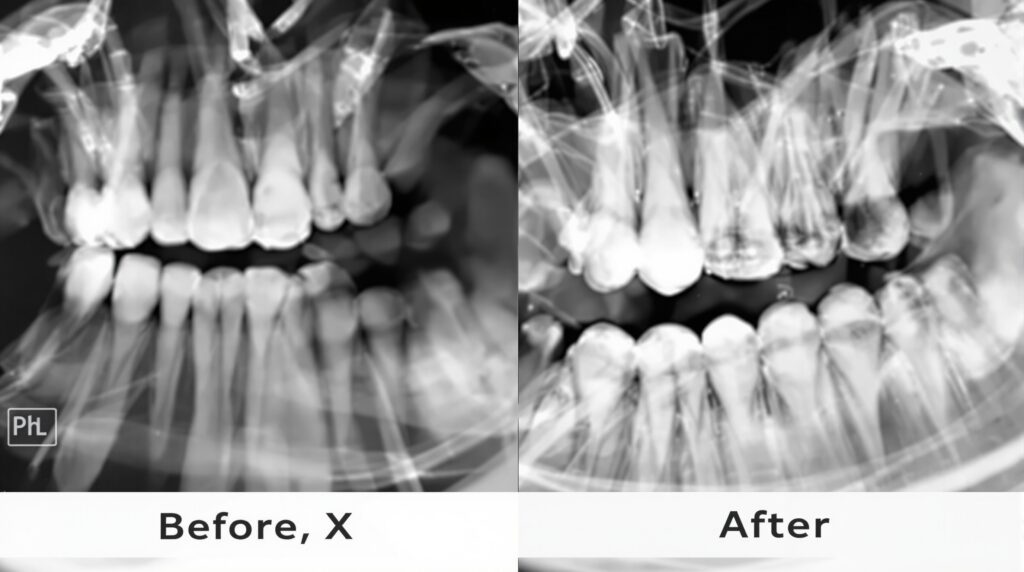

The integration of smartphone technology into dental practice has transformed clinical photography from a specialized skill into an accessible, everyday tool. Modern dental professionals are discovering that high-quality smartphones can deliver professional-grade images that enhance patient communication, treatment planning, and documentation.

Traditional dental photography required expensive DSLR cameras, specialized macro lenses, and extensive training. Today’s smartphones, equipped with advanced camera sensors, computational photography, and professional apps, have democratized clinical imaging. The iPhone 15 Pro and Samsung Galaxy S24 Ultra now offer macro capabilities, RAW image capture, and precise color reproduction that rivals traditional dental cameras.

Achieving professional results with smartphones requires understanding proper techniques and lighting principles. The key to exceptional clinical photography lies in consistent lighting, proper positioning, and standardized protocols.

Positioning and angles remain critical for reproducible documentation. Establishing standardized photo sequences—including frontal, lateral, and occlusal views—ensures comprehensive documentation that meets both clinical and legal requirements.